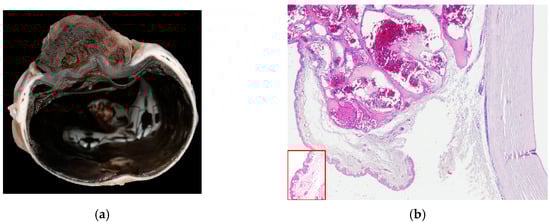

Unlocking Tumor Aggressiveness in Endometrial Cancer: AI-Driven PET/CT Radiomics and Machine Learning for Prediction of High-Risk Tumor Histology

Purpose: Accurate preoperative risk stratification in endometrial cancer (EC) is essential for guiding surgical and therapeutic decisions. This study aimed to evaluate the discriminative performance of [18F]-FDG PET/CT-derived radiomic features combined with machine learning models for differentiating low-risk (LRH-EC) and high-risk histology (HRH-EC) subtypes. Methods: A total of 159 patients with histopathologically confirmed EC who underwent preoperative [18F]-FDG PET/CT were retrospectively analyzed. Radiomic features were extracted using LIFEx version 7.4.0 software following IBSI guidelines. After FDR correction and Pearson correlation–based redundancy reduction (|r| > 0.80), 16 radiomic features were retained for modeling. Three feature configurations (Conventional PET parameters, Radiomics16, and Combined) were evaluated. Machine learning models were developed using stratified 5-fold cross-validation. Model performance was assessed using AUC, accuracy, sensitivity, specificity, F1-score, Wilson confidence intervals, DeLong’s test, and McNemar’s test. Results: Artificial Neural Network (ANN) (AUC = 0.709) and Random Forest (RF) (AUC = 0.686) achieved the highest discriminative performance within the Radiomics16 feature set. No statistically significant superiority between algorithms or feature configurations was observed by DeLong analysis. However, McNemar’s test demonstrated significant patient-level classification differences for the Combined ANN model (p < 0.001). NGTDM_Coarseness and SUVmin emerged as the most influential features, reflecting tumor heterogeneity and metabolic activity. Conclusions: [18F]-FDG PET/CT-based radiomics combined with machine learning provides moderate yet consistent discrimination between LRH-EC and HRH-EC. While external validation is required, this approach may support noninvasive preoperative risk stratification in endometrial cancer. Full article